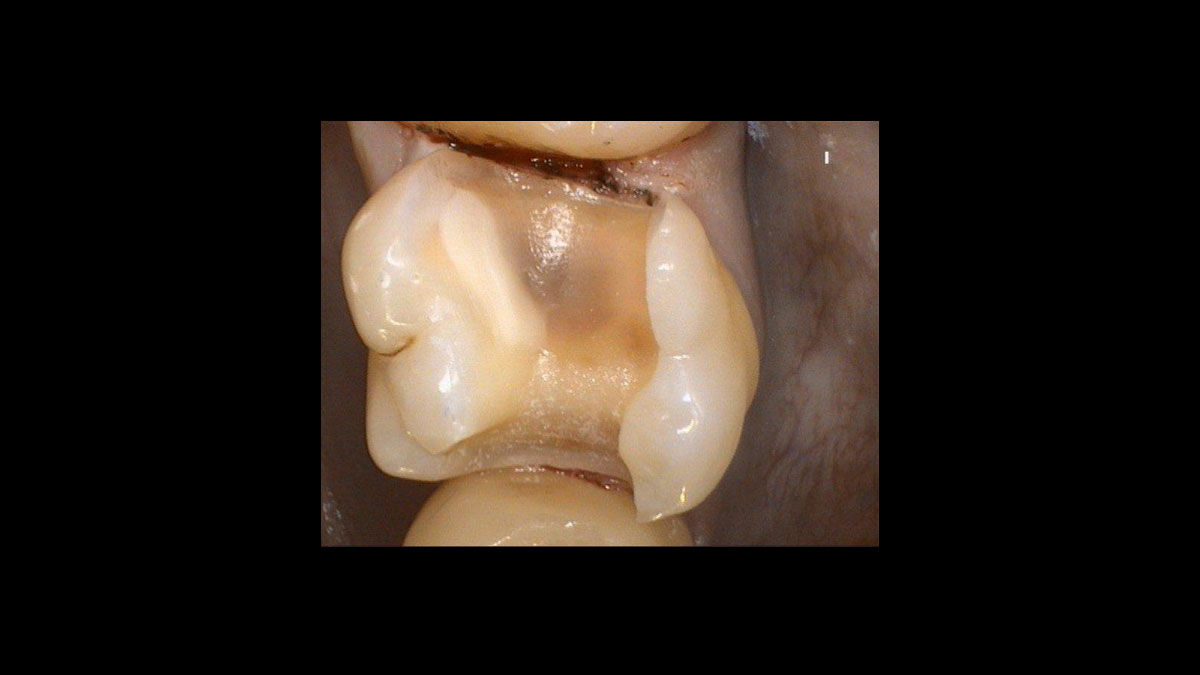

Exposition d’une dent déplacée